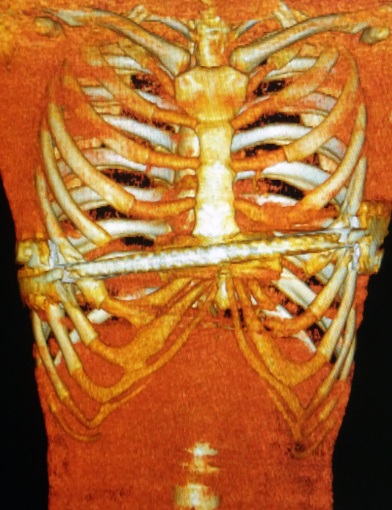

术前行X线检查:正位片提示胸壁内有钢板一条,钢板位置倾斜,脊柱轻度侧弯(图4)。侧位片提示前胸壁下部局部凹陷,钢板位置偏斜(图5)。行CT检查:可见胸壁内钢板影。横截面未见明显凹陷,但不同水平前后径明显不同(图6-10)。三维重建提示钢板影,前胸壁凹陷畸形(图11,12,13)。心电图及腹部超声检查未发现异常。

图12,胸壁组织三维重建图:钢板融入胸壁软组织。

图13,胸壁组织三维重建图:钢板倾斜,两端融入软组织。